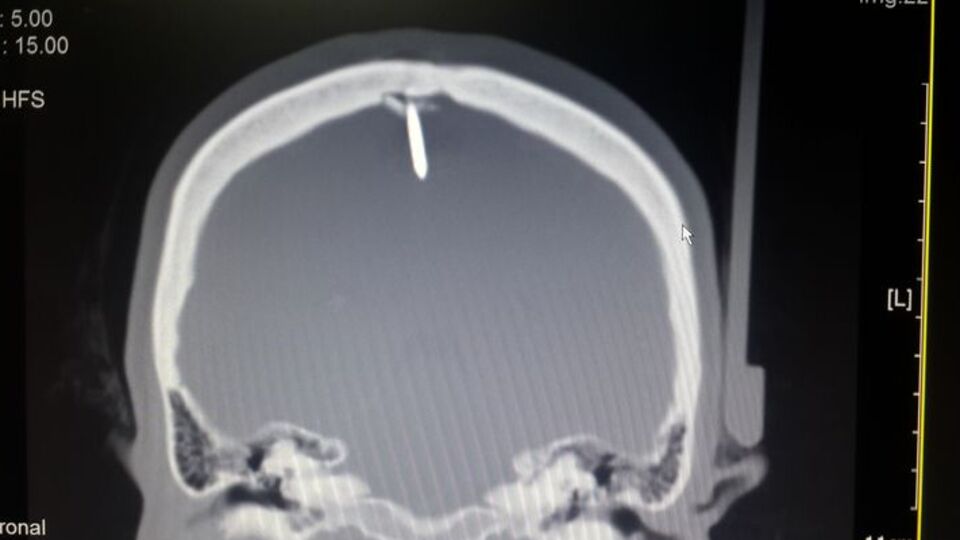

Bir fabrikada işçi olarak çalışan 45 yaşındaki Şahin, 14 Şubat'ta ayağının kayması sonucu çivi tabancasının üzerine düştü. Kafasına montaj çivisi saplanan kadın, işyerindeki arkadaşlarının yardımı ile acil servise kaldırıldı. Çekilen beyin tomografisinde, kafatasını delen 2,5 santimetre uzunluğundaki çivinin bir kısmının beyne de zarar verdiği belirlendi.

Beyin ve Sinir Cerahisi Anabilim Dalı Başkanı Yrd. Doç Dr. Varol Aydın ile Beyin Cerrahi Anabilim Dalı Öğretim Üyesi ve hastane Başhekim Yardımcısı Doç. Dr. Ali Yılmaz, yoğun bakım servisine yatırılan ve beyin anjiyosu yapılan Şahin'in kafasındaki çivinin ameliyatla alınmasına karar verdi. Çivi, 16 Şubat'ya yapılan yaklaşık 1 saatlik ameliyatla kafatasından çıkarıldı.

Yrd. Doç Dr. Aydın, bu tür bir kaza ile ilk kez karşılaştığını belirterek, şunları kaydetti: "Çivinin girdiği bölgeyi hastayı uyuttuktan sonra yarmaya başladık. Çok risk taşıyan bir operasyon olduğu için en ufak bir hataya meydan vermeden kafasından bir parça kemik çıkartıp pencere açtık. Damarları koruyan bölgeye zarar verilmesi halinde hastanın yüksek hayati risk taşıması söz konusuydu. Çivinin beynin motor fonksiyonları yöneten kısmına sadece birkaç milimetre uzaklıkta olması bizi korkutsa da son derece başarılı bir operasyonla 2.5 santim uzunluğundaki çiviyi çıkarttık. Daha sonra aynı bölgeyi yine operasyonla kapattık."